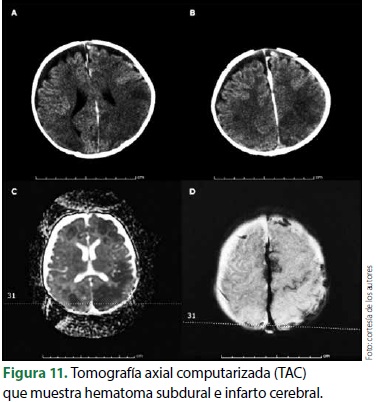

El sufrimiento súbito y grave del sistema nervioso central se puede observar en niños menores de 2 años como una consecuencia del sacudimiento severo del cráneo y, en ocasiones, por azotamiento de todo el cuerpo en una superficie dura. Esta entidad se denomina "síndrome del niño sacudido" (SNS), del que se distinguen 2 modalidades: el niño que únicamente es sacudido (SNS) y el que además es azotado (SNSa). La primera forma es la más frecuente y se observa en 2 terceras partes de los casos.

Lo característico es que los niños víctimas de SNS no tienen una expresión visible de daño físico a pesar de su extrema gravedad clínica. Presentan sufrimiento agudo del sistema nervioso central expresado por crisis convulsivas de presentación súbita o pérdida del estado de alerta, así como insuficiencia cardiorrespiratoria súbita.

La forma menos frecuente del síndrome es SNSa, que es igual o más grave que la anterior pero, en este caso, con lesiones en la bóveda craneana o de uno o varios huesos largos. En ambas modalidades pueden existir fracturas en la unión costovertebral posterior12 (figuras 8-11) (9, 10).